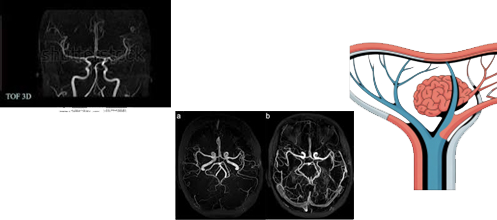

Vega TOF Screening

Time-of-flight vascular imaging for rapid cerebrovascular assessment without contrast agents. Ideal for stroke risk evaluation and vascular screening programs.

TOF-MRI: The Game-Changing Screening Solution

What Makes TOF-MRI Different?

Time-of-Flight Magnetic Resonance Imaging (TOF-MRI) is a revolutionary screening technology that creates crystal-clear pictures of your brain’s blood vessels using flowing blood as a natural contrast agent. This ingenious approach eliminates the need for dyes, radiation, or invasive procedures.